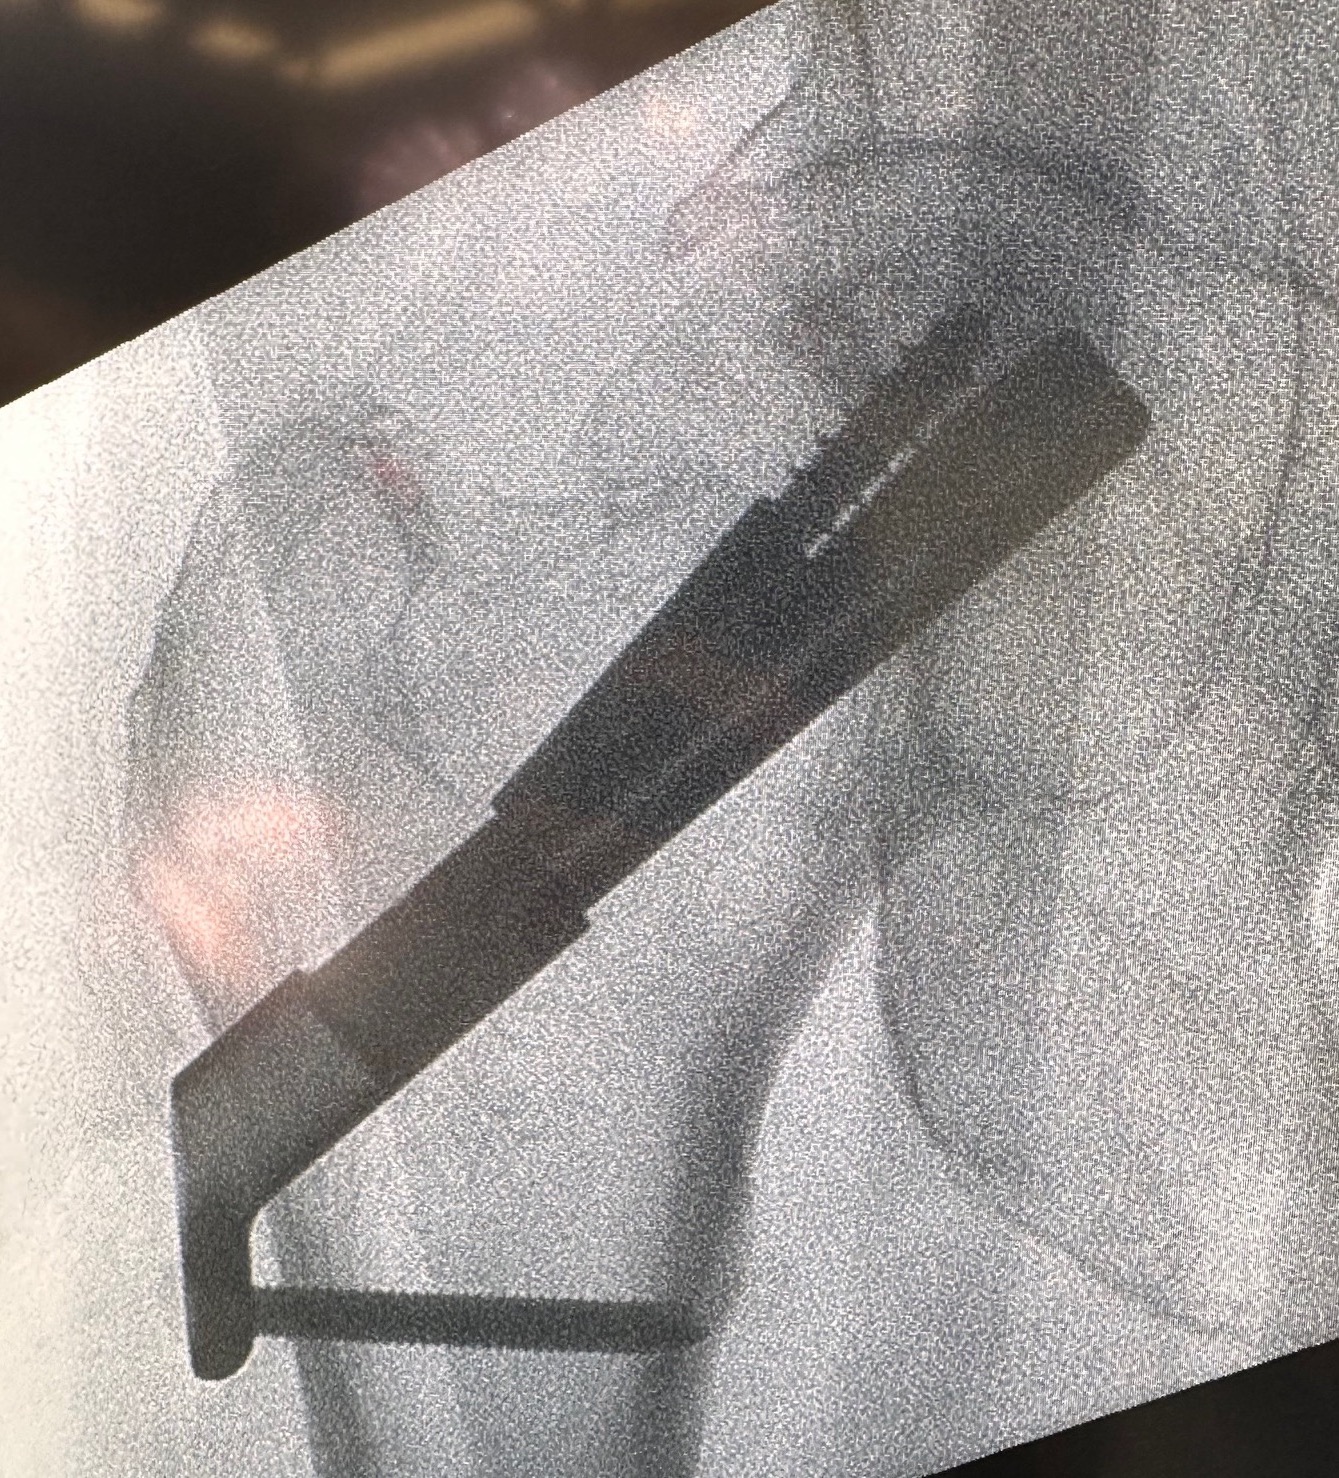

DHS and derotation screw

Youtube step by step sawbone guide

Sliding hip screw (SHS/DHS) + derotation screw